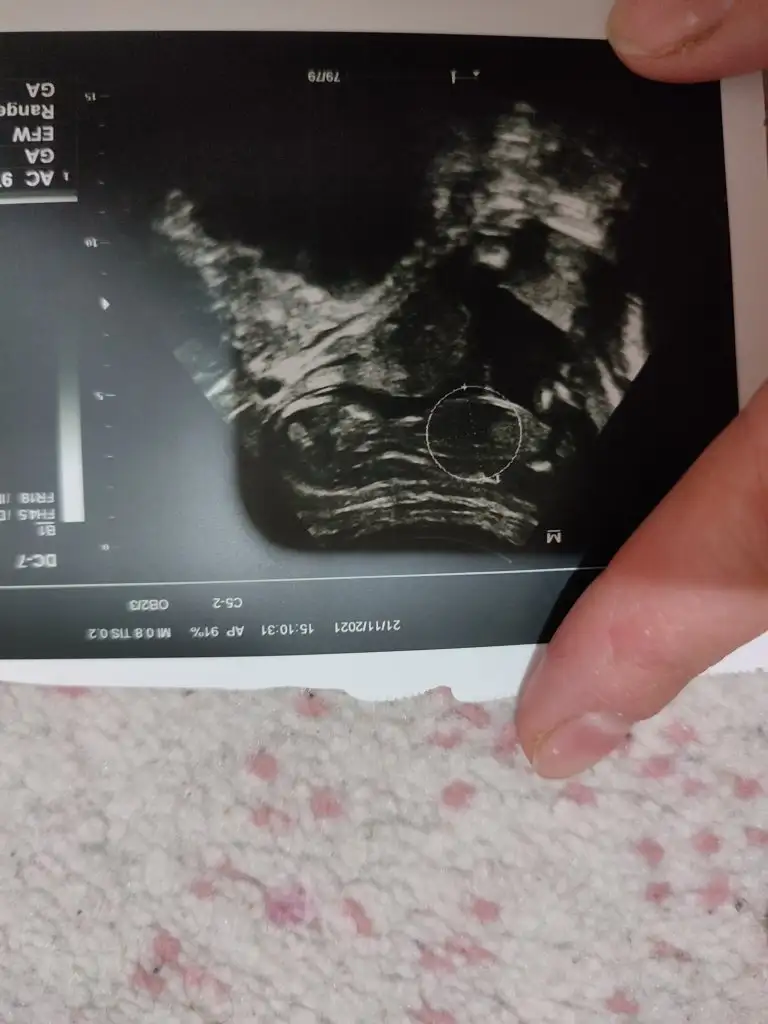

kemik yapisina gore kiz gibi

yahut erkege benziyor diyorlar ya

iste o nub teorisi kizlar dr buradan yola cikiyor

Bana iki kez kiz demistiniz ama oglum olacak ♥Emin olamadım ama sanki kız gibi

Sağlıkla gelsin oğlusun emin olamadım çünkü nub bölümü silik görünüyordu tekrar baktım evet silik görünüyorBana iki kez kiz demistiniz ama oglum olacak ♥